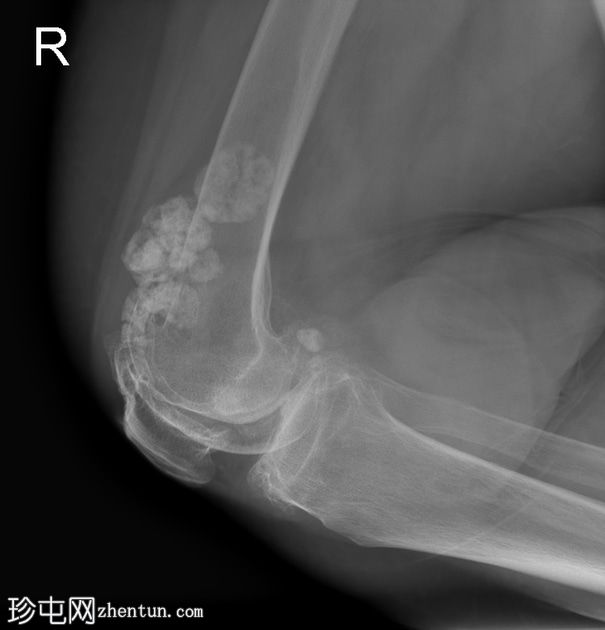

双膝X线片

X线片

正位片

侧位片

双侧胫股关节间隙明显变窄,伴软骨下硬化。

双侧髌股关节间隙变窄。双侧股骨和胫骨关节周围骨赘及髌骨骨赘。

右侧股骨远端软组织内可见多发致密钙化分叶状病变。未见骨折、骨膜反应或骨损伤。无内翻或外翻畸形。

本病例展示了继发性滑膜软骨瘤病伴严重膝骨关节炎的典型

影像

学表现。